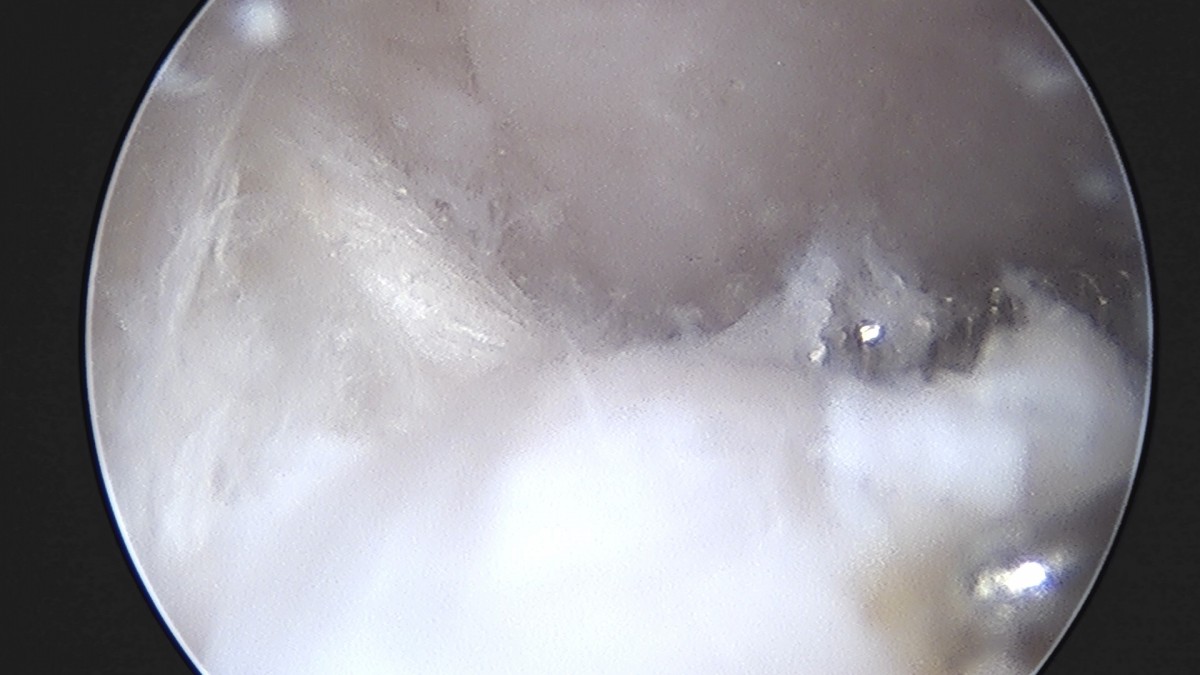

이재상원장님 무릎 반월상 연골판 절제술 박대O 환자

dae765e4d9ac96aee867c9d6292d8784_1758005044_6408.jpg